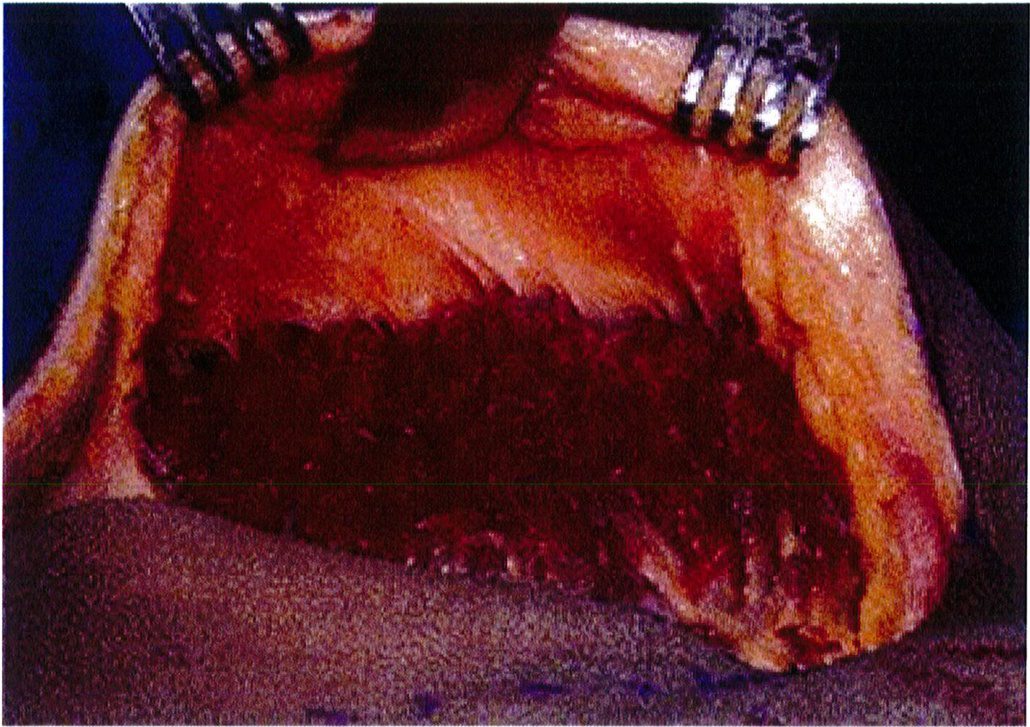

Hình. 13. Bóc tách lớp dưới cân của một tử thi và nâng lên để quan sát. Đường rạch lớn như thế này chỉ với mục đích quan sát và minh họa quá trình phẫu thuật, không áp dụng trong lâm sàng. Trong thực tế, một đường rạch tiêu chuẩn chỉ dài 6-7 cm. (From de la Pena JA. Subfascial technique for Nâng mông. Aesthet Surg J 2004;24:268; đã xin phép trước khi đăng tải.)